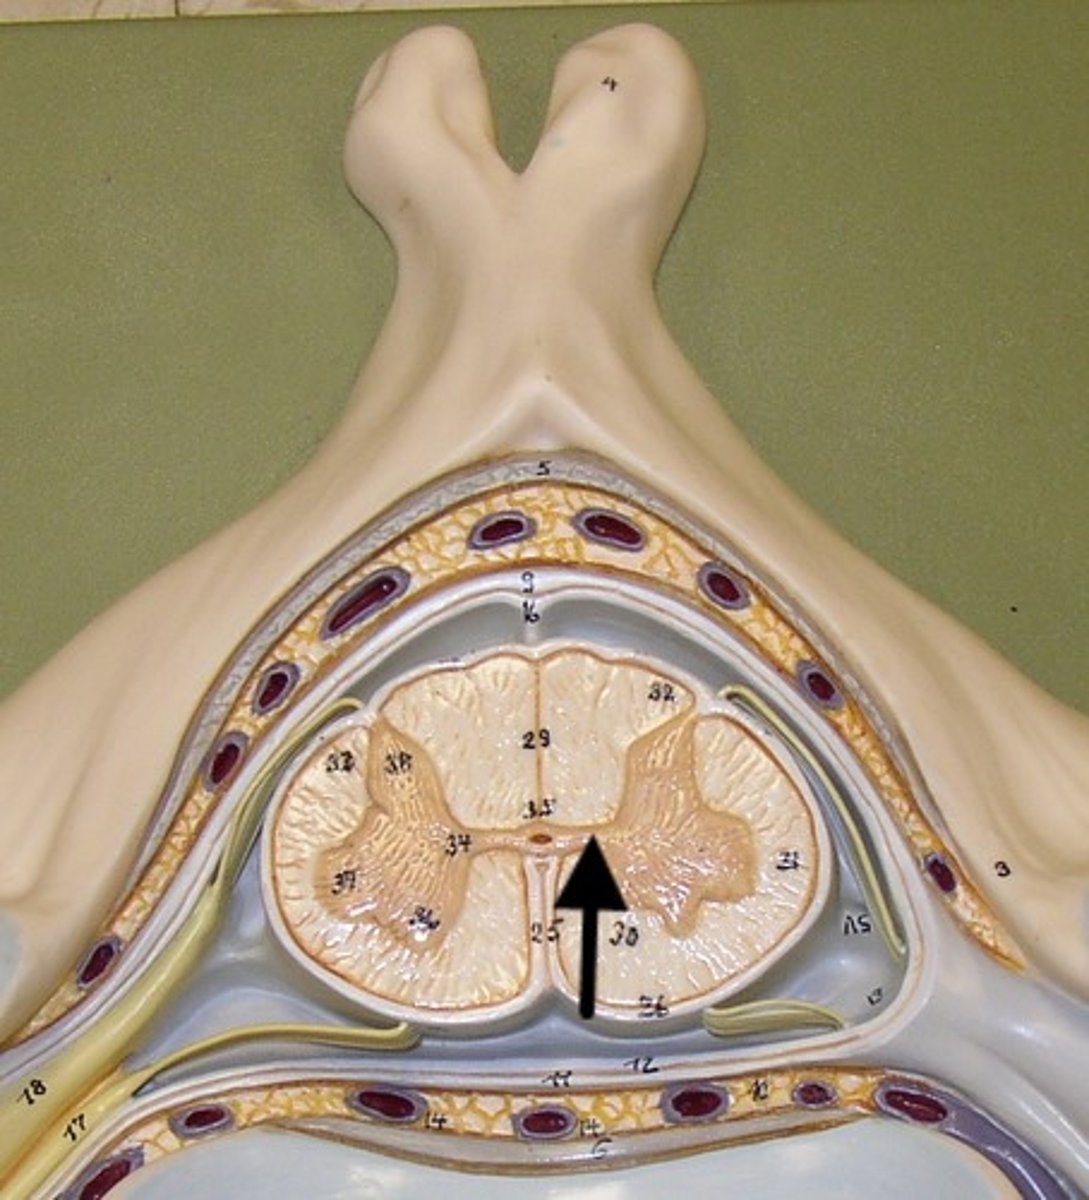

central canal

Hole in the center

Name this passageway

gray commissure

Part of grey matter connecting the two halves of the grey matter in spinal cord